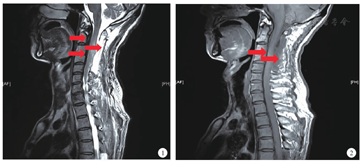

患者男,57岁,主因"颈部及双肩疼痛伴四肢麻木4年,左侧肢体活动受限,排便困难1年"入院。患者于2010年出现颈部及双肩部疼痛,伴四肢麻木,药物治疗效果不佳,于我院查颈胸段MRI示"颈胸段椎管内脊髓前方弥漫性条状低信号,增强扫描明显强化,相应水平脊髓受压,脊髓内见弥漫性长T1稍长T2信号影,C2~T8椎管内占位,淋巴瘤?炎性病变?(见图1,图2)" 。2010年3月于我院行"C1~5,T5~7前方肿物切除,椎板减压术" ,术中见"剪开背侧硬膜后脊髓外膨明显,右侧轻牵拉脊髓,见C1~4腹侧病变,质硬,红褐色,扁平与硬膜不能分开" ,病理提示"送检组织为慢性非特异性炎,纤维组织增生,灶状小血管增生,免疫组织化学CD3灶状(+),CD20灶状(+),CD4少数(+),CD8少数(+),CD117(-),s-100(-),CD10(-),EMA灶状(+),Ki-67少数(+),比较符合脑脊髓膜炎,不能除外炎性脑膜瘤" 。术后患者上述症状未好转,逐渐出现左侧肢体无力,活动受限,大小便排便费力,于2014年11月收入我院。既往抑郁病史,长期药物控制。查体:神志清楚,生命体征平稳,心、肺、腹查体未见明显异常。右侧肢体针刺觉减退,左上肢肌力Ⅲ级,左下肢肌力Ⅳ级,左下肢巴氏征阳性。辅助检查:血、尿、便常规及生化检查均未见异常,肿瘤标志物正常。ANA斑点胞质型1∶80,抗dsDNA抗体阴性,ANCA阴性,血清免疫球蛋白亚型IgG1~4均在正常范围。腰椎穿刺检查示脑脊液透明清亮,压力正常,脑脊液常规及生化正常。腹部B超示胆囊多发息肉,胰腺形态正常,胰管无扩张。颈胸段MRI示:C1~2,T5~7脊髓混杂长T2信号,范围较前扩大。头颅MRI脑白质轻度脱髓鞘,未见硬脑膜增厚。腰骶MRI示:L3~5,L5~S1椎间盘突出,未见椎管内占位。复核2010年手术病理切片加染IgG4免疫组织化学:组织挤压明显,可见较多淋巴细胞、浆细胞浸润,间质纤维化、局灶偶见席纹样改变,未见确切静脉炎改变,IgG4+细胞数量升高,个别区域达40/HP(IgG4+细胞浸润面积约占1/3),IgG4+/IgG+细胞比例<40%,病理学表现不足以确诊IgG4相关硬化病变。考虑诊断为特发性肥厚性硬脊髓膜炎(idiopathic hypertrophic spinal pachymeningitis,IHSP),予地塞米松10 mg,每日1次静脉输液1周后患者症状无明显改善,改为泼尼松60 mg,每日1次口服,加用吗替麦考酚酯(骁悉)500 mg,每日2次口服后出院。院外患者吗替麦考酚酯口服1个月后停药,泼尼松应用1年,逐渐减量至7.5 mg/d停用,长期口服B族维生素,1年后随访,患者左上肢肌力较前无明显改善,小便费力较前加重。